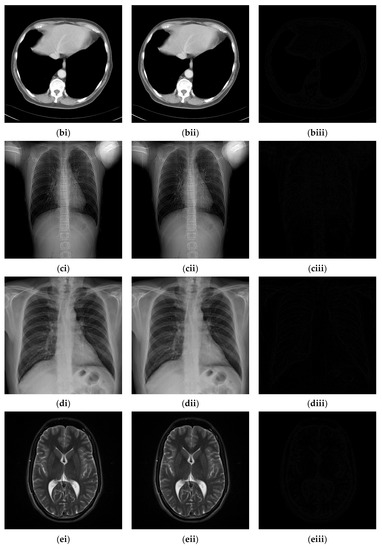

4.2. Experimental Results for Medical Images

Since the interpolation-based RDH schemes are designed for the special purpose of embedding patient information into medical images, the performance of our proposed adaptive RDH scheme on medical images is the main concern. Figure 11 shows the original image and its corresponding confidential image with 2 bpp secret data embedded, and images showing the difference between the original medical images and their confidential images. The difference images (aiii–fiii) in Figure 11 show almost nothing, which indicates that the proposed scheme does not look much different from the original image after hiding and will not draw the eavesdropper’s attention.

Figure 11.

The original images, the confidential images, and the different images; (ai–fi) The cover images; (aii–fii) The confidential images; (aiii–fiii) The difference between the cover images and the confidential images.